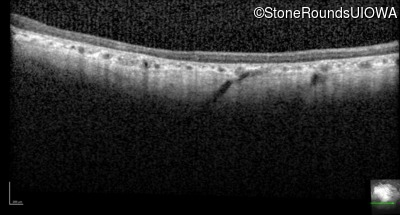

Optical Coherence Tomography - Right - 10/200 sc

Exemplar / OCT Stack